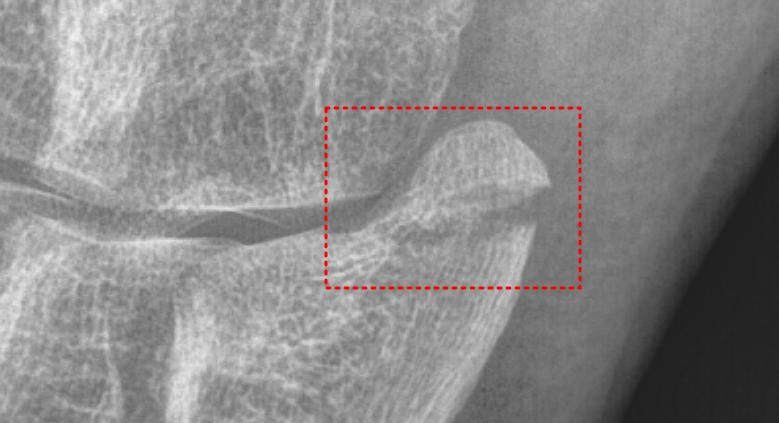

• 2번 째 사진

5번 중족골 기저부 골절에 따른 수술 여부는 단순 주상골 골절인 같은 인대가 뼈를 잡아당기면서 생기는 골절이나 미세한 골절이면 비수술적 치료도 충분히 가능하나 비체중부 골절이나 분쇄골절 시에는 자연 회복이 어렵기 때문에 수술이 필요할 수 있는 상황입니다.

사진상으로는 골절 부위가 뼈의 중심에서 다소 떨어져 있으며, 일부 변위도 있는 것으로 보입니다.

비수술적인 치료도 고려될 수 있지만 아무래도 수술을 하시는게 회복기간 및 예후가 좋을 것으로 생각됩니다.